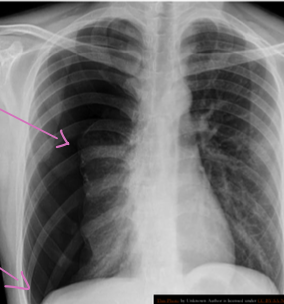

What is the abnormality in CXR? Hilar lymphadenopathy (enlarged lymph nodes in the hila of both lungs)

-

What is the most likely diagnosis? Sarcoidosis; lump

Bilateral Hilar Lymphadenopathy: Causes

| Category | Causes |

|---|---|

| Sarcoidosis | Sarcoidosis |

| Infection | * Tuberculosis * Fungal infection * Mycoplasma * Intestinal Lipodystrophy (Whipple’s disease) |

| Malignancy | * Lymphoma * Carcinoma * Mediastinal tumors |

| Inorganic dust disease | * Silicosis * Berylliosis |

| Extrinsic allergic alveolitis | * Such as bird fancier’s lung |

| Less Common Causes | * Churg-Strauss syndrome * Human immunodeficiency virus * Extrinsic allergic alveolitis * Adult-onset Still’s disease |